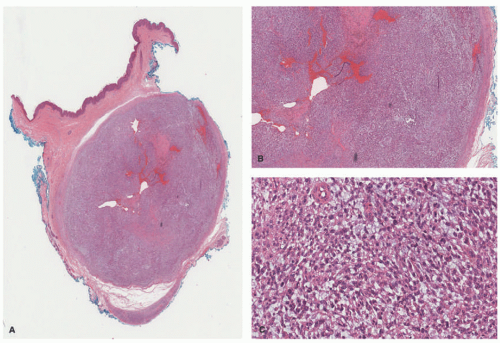

Pathologically, the schwannoma is a well-circumscribed, encapsulated spindle cell neoplasm to be differentiated from the myriad of other similarly appearing related and unrelated tumors (Figure 24-7). In those schwannomas whose capsule is not apparent, the cellular variant with or without mitotic activity, nuclear enlargement, and hyperchromatism or one of the several less common variants including the plexiform (Figure 24-8), myxoid-reticular (Figure 24-9), and glandular subtypes can be a histopathologic challenge.

When a schwannoma presents in a child, it is often in the setting of NF2 and may present in the subcutis and less often in the dermis alone, with the exception of the plexiform schwannoma (PS) with its predilection for the skin and underlying soft tissues.31 This tumor is seen in children and is associated with NF2 and schwannomatosis.32,33,34 PS is often cellular and displays some nuclear pleomorphism and mitotic activity (5 or less per high-power field [HPF]); these features in the context of PS are not indicative of malignancy because this tumor behaves in an entirely benign fashion (Figure 24-8). Unlike the conventional schwannoma, a capsule is not present in most PSs. The encapsulated nature of PS may be inapparent.

FIGURE 24-7. A-D, Schwannoma presenting on the upper eyelid of an 11-year-old male with NF2. A, The well-defined peripheral capsule is shown together with the inked margin. B, The fibrillary background is composed of cytoplasmic processes. The nuclei are arranged in small aggregates suggesting the formation of pseudorosettes. C, Unlike the neurofibroma, S100 protein is strongly and diffusely positive. D, Collagen type IV immunostain demonstrates the characteristic pattern of basement membrane positivity.

FIGURE 24-8. A-D, Plexiform schwannoma. Numerous plexiform profiles are composed of uniform spindle cells with focal Verocay body formation. Antoni A and Antoni B patterns are seen. Digital slides courtesy of Path Presenter.com.

FIGURE 24-8. (continued)